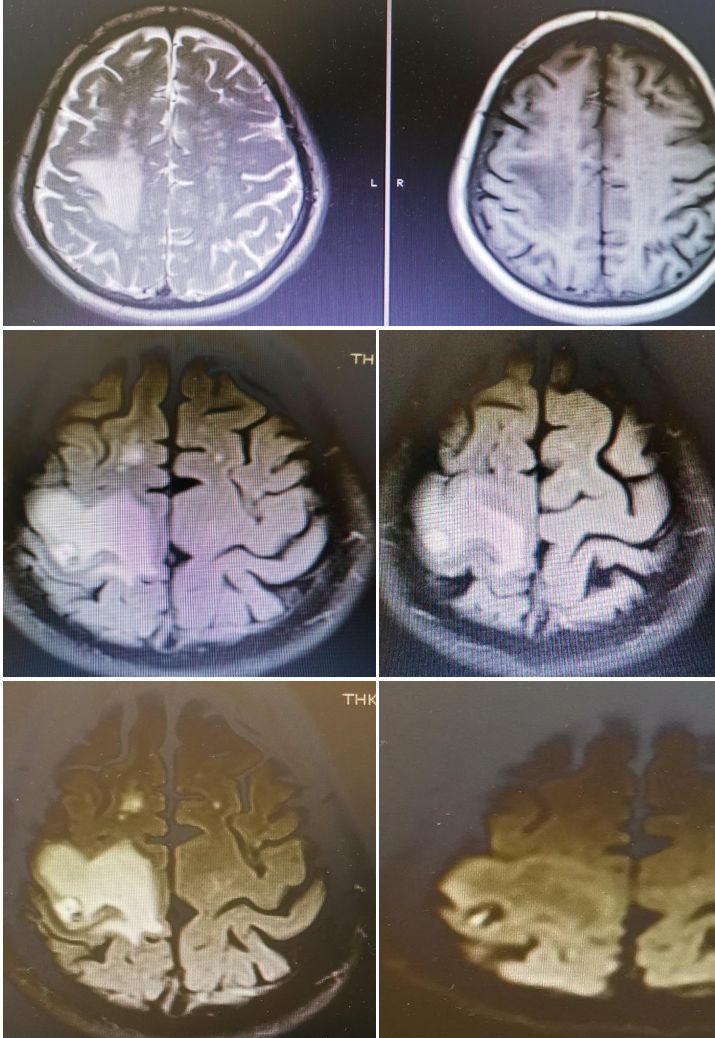

发病24小时磁共振:

答案:脑型脂肪栓塞综合征。患者做了自体脂肪填充术。脂肪栓塞综合征(fat embolism syndrom,FES)是指直径为10~40μm的血管内脂肪颗粒阻塞血管腔而引起的一系列病理生理改变的临床综合征。FES常发生于骨创伤及骨手术病人。FES潜伏期为6~24h,FES 的典型三联征为低氧血症、意识障碍和瘀斑。